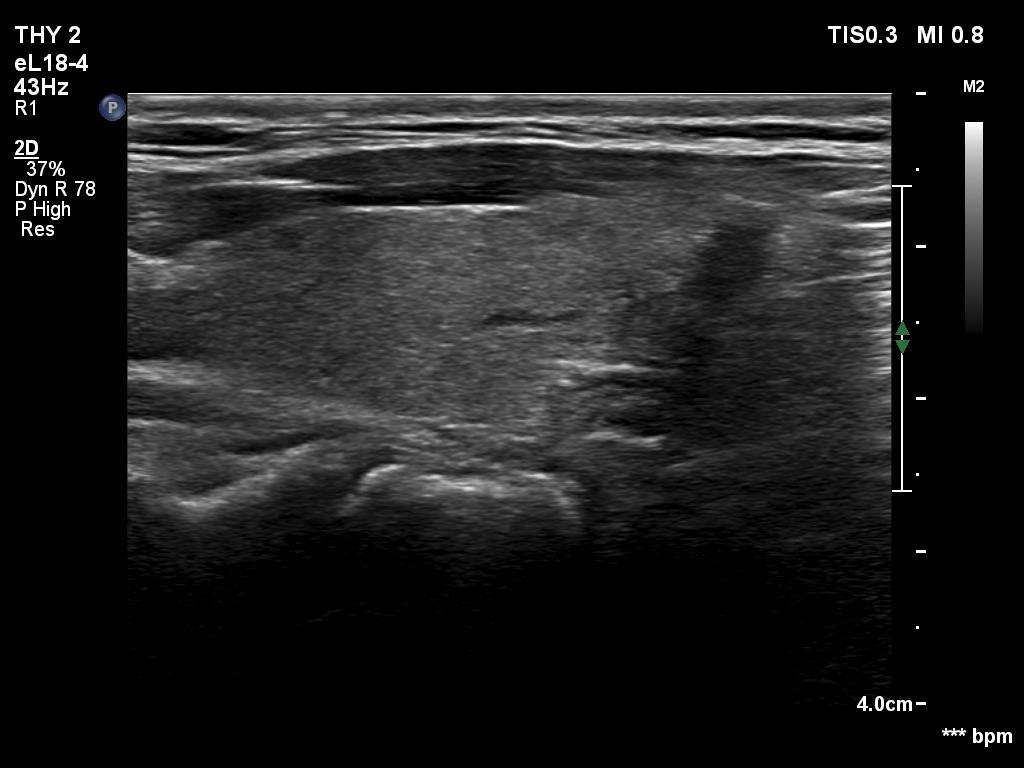

TIRADS - case 497 (ultrasonographic picture 6)

Left lobe, longitudinal scan.